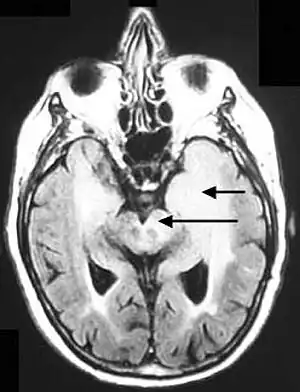

Axial fluid-attenuated inversion recovery MRI image demonstrating tumor-related infiltration involving both temporal lobes (Short arrow), and the substantia nigra (Long arrow).

Before the advent of MRI, diagnosis was generally not established until autopsy. Even with MRI, however, diagnosis is difficult.[8] Typically, gliomatosis cerebri appears as a diffuse, poorly circumscribed, infiltrating non-enhancing lesion that is hyperintense on T2-weighted images and expands the cerebral white matter. It is difficult to distinguish from highly infiltrative anaplastic astrocytoma or GBM.